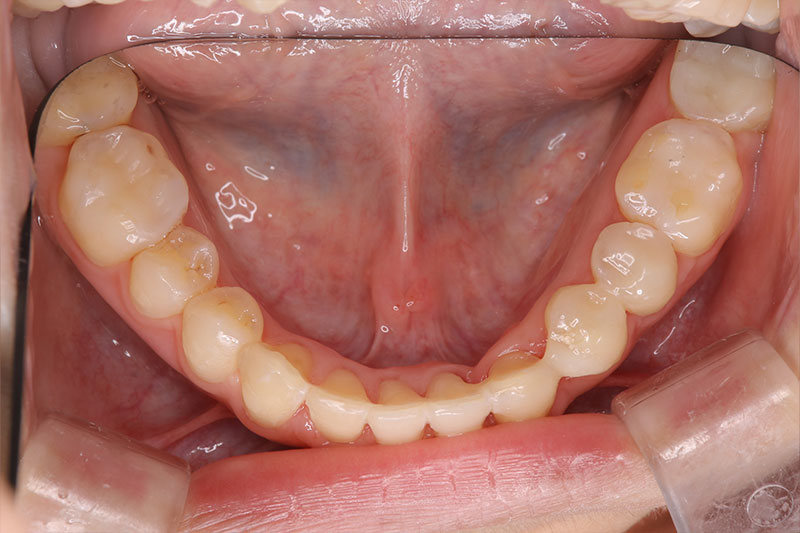

症例3:50代男性/歯がグラグラしてよく噛めない

初診時

治療中

治療後

| 治療概要 | 重度の歯周病のため、歯周基本治療後にマルチブラケット法を用いたワイヤー矯正による全体矯正を行い、矯正治療後にダイレクトボンディング法による保存修復治療と、インプラントを用いた欠損補綴治療を行った |

|---|---|

| 矯正治療法 | 部分矯正(ワイヤー) |

| 矯正治療期間 | 動的期間約6ヶ月、保定期間約6ヶ月、計1年間 |

| 治療回数 | 28回 |

| リスクと副作用 | 矯正装置が口腔粘膜に当たることによる口内炎、お口の清掃不良による虫歯・歯周病の発生、インプラント周囲炎 |

| 費用 | ワイヤー矯正:88万円 |